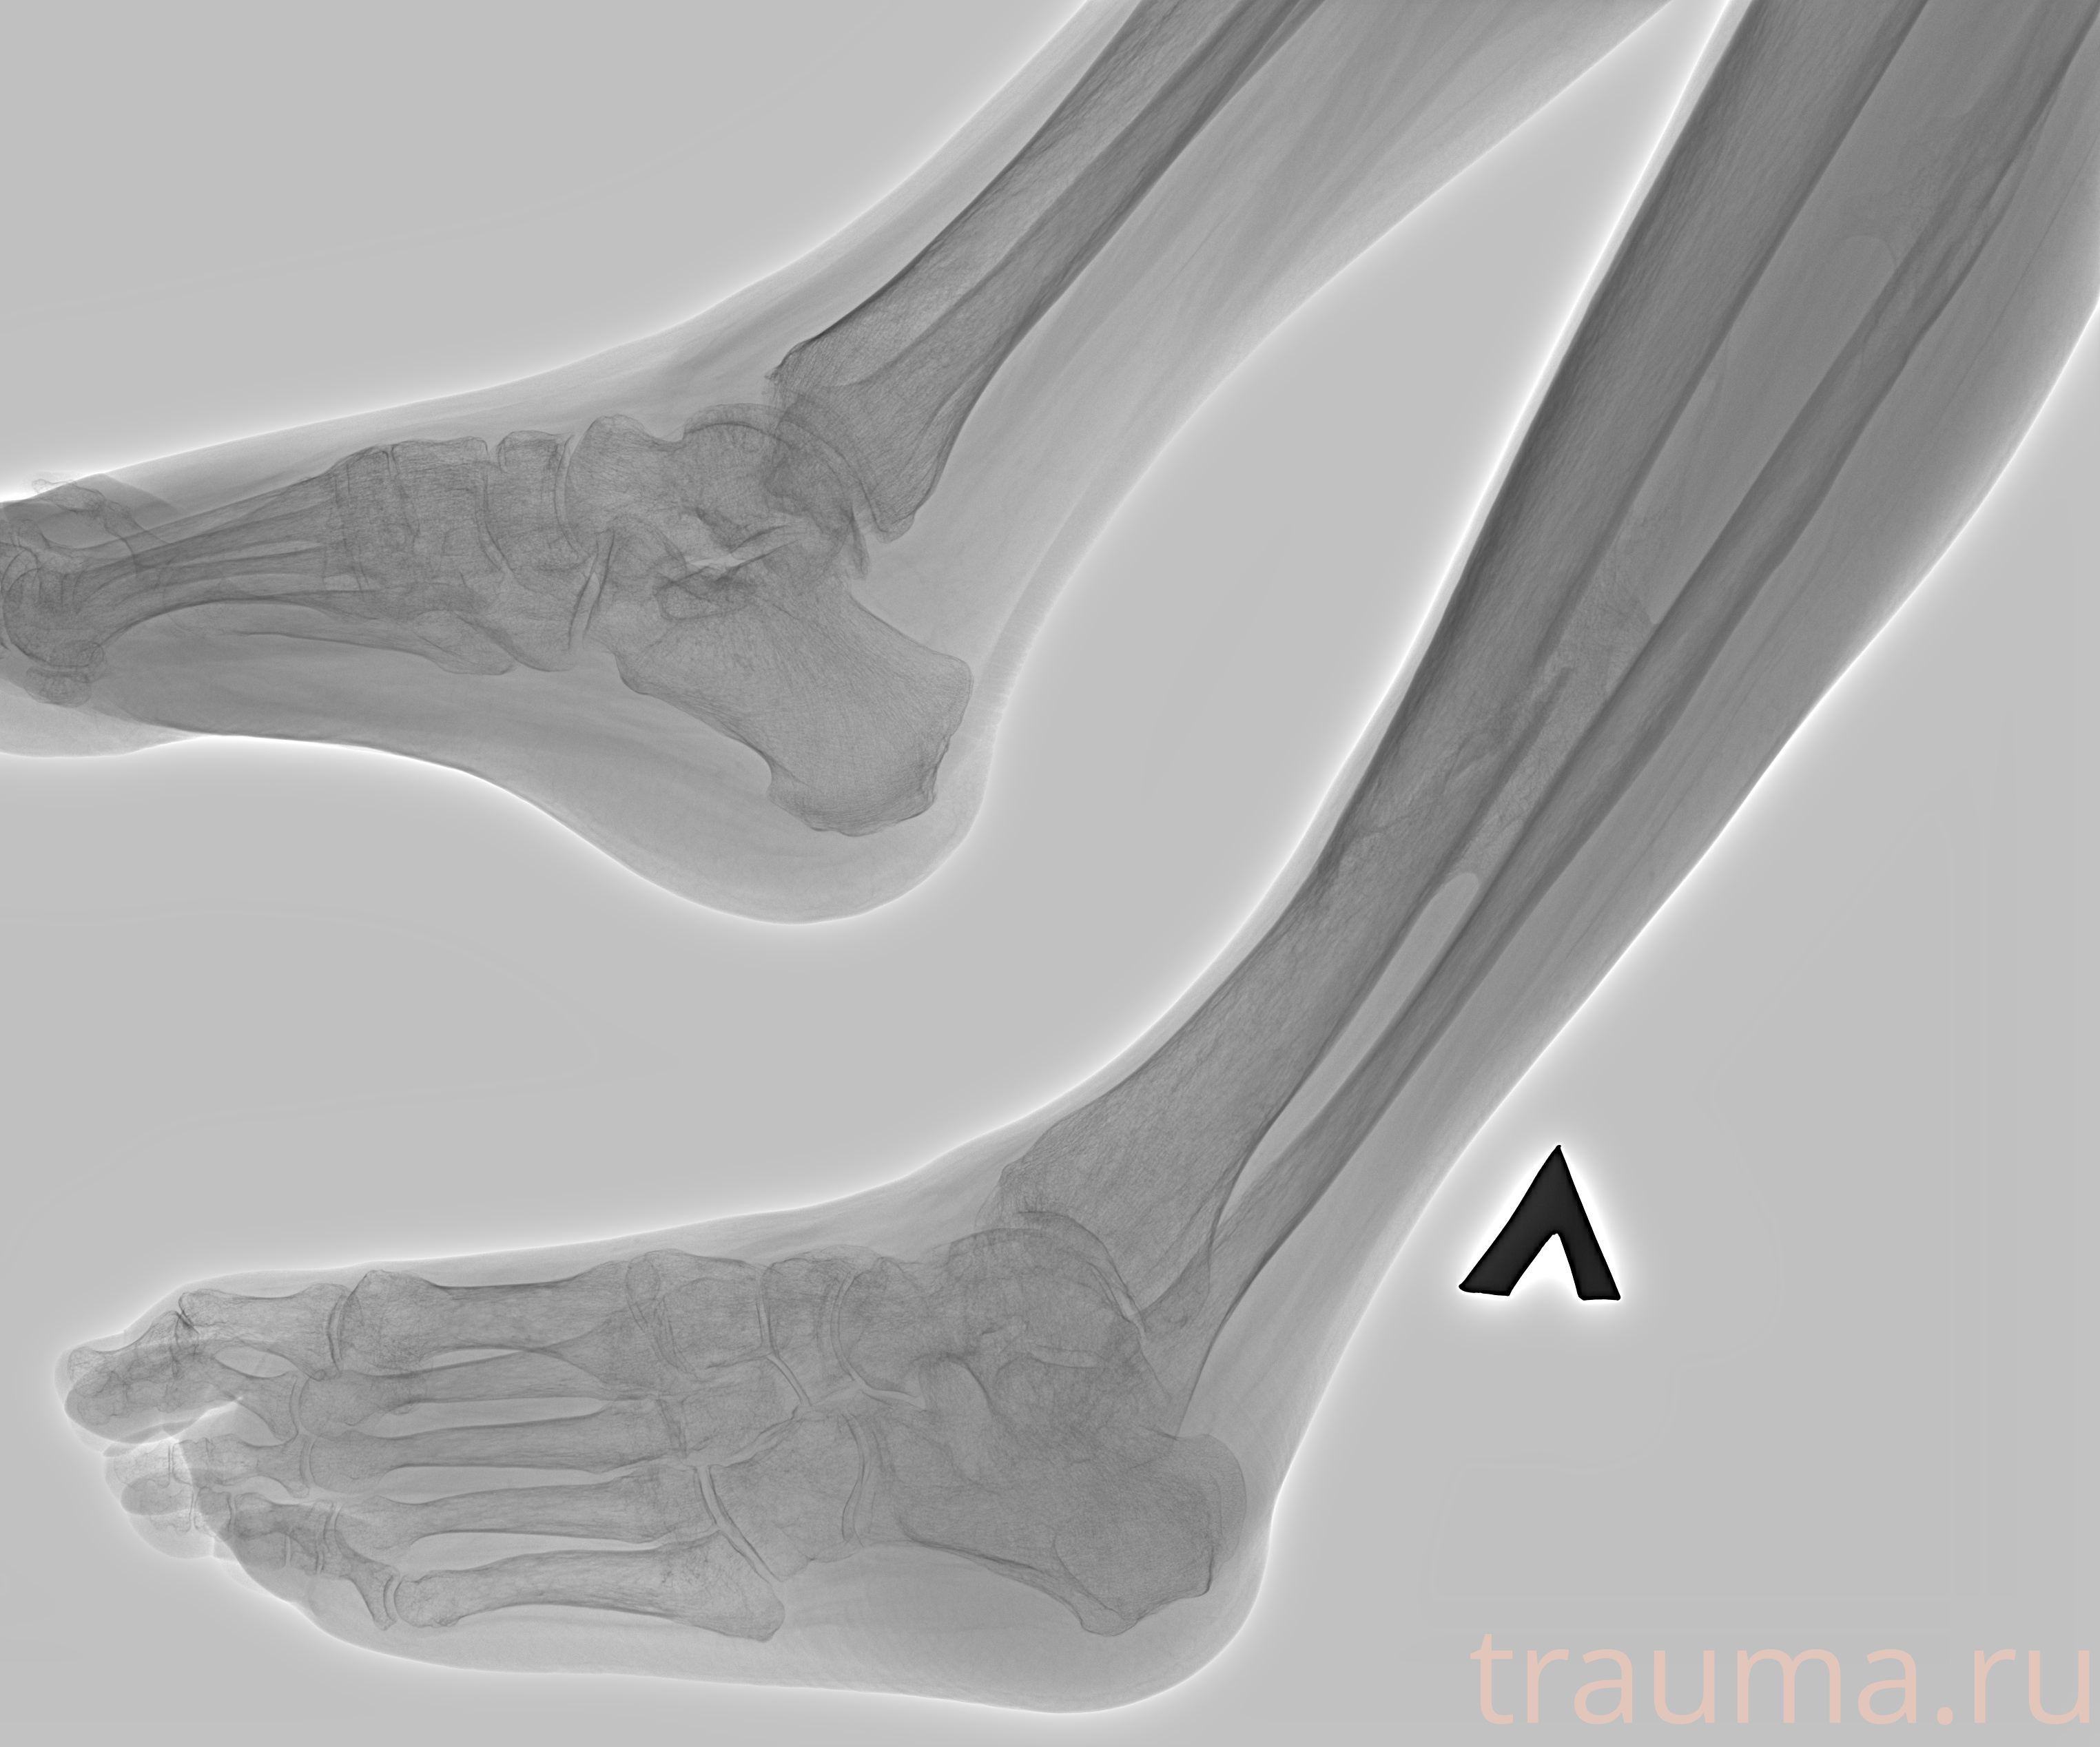

Рентгенограммы

Рентген на дому: по вашему адресу приезжает врач-рентгенолог, травматолог-ортопед с мобильным рентгеновским аппаратом, проводит диагностику травмы или заболевания, делает необходимые рентгенограммы, дает рекомендации по дальнейшему лечению. Получить качественные снимки в домашних условиях возможно благодаря уникальной методике, разработанной МосРентген Центром для института  Склифосовского